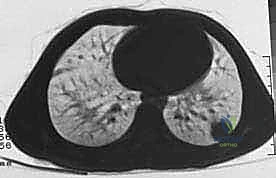

| الانتشار (النقائل) | لا تنتشر لأعضاء أخرى | تنتشر غالباً إلى الرئتين أو عظام أخرى |

* العلاج الكيميائي قبل الجراحة (Neoadjuvant Chemotherapy): يُعطى لتصغير حجم الورم، مما يسهل عملية الحفاظ على الطرف، ويقتل الخلايا السرطانية الدقيقة المنتشرة في الدم.

* العلاج الإشعاعي (Radiotherapy): يُستخدم غالباً في ساركوما الأنسجة الرخوة لتقليل احتمالية عودة الورم موضعياً.

يتم تقييم مدى استجابة الورم للعلاج الكيميائي (Tumor Necrosis Rate) بعد الاستئصال، وهو مؤشر قوي لفرص الشفاء التام.